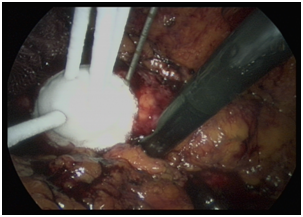

Probes to measure the freezing temperature achieved are also placed, one within the centre of the tumour and the other about a centimetre beyond the tumour circumference. Usually two cycles of freezing with Argon and two cycles of thawing with helium gas are employed. When the tumour is frozen, a spectacular white mound is usually seen at laparoscopy (Figure 1). The needles are removed, post-procedure and any bleeding is usually effectively controlled by compression. The calibre of the needles used and the techniques employed, vary slightly between different machines used. Open surgical cryoablation when necessary, is also another available option.

Figure 1: Laparoscopic cryoprobes placed in renal tumour, producing a white mound.